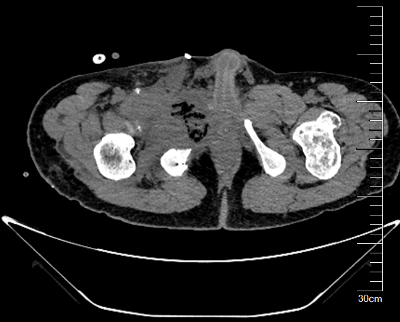

图片 4.png图片 5.png图片 6.png

术前MR